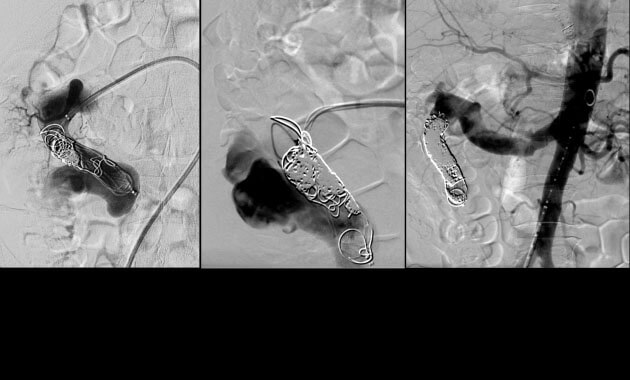

Vascular Malformation

- Conditions: Arteriovenous malformation (AVM), Hereditary Hemorrhagic Telangiectasia (HHT)

- Services: Angiography, embolization